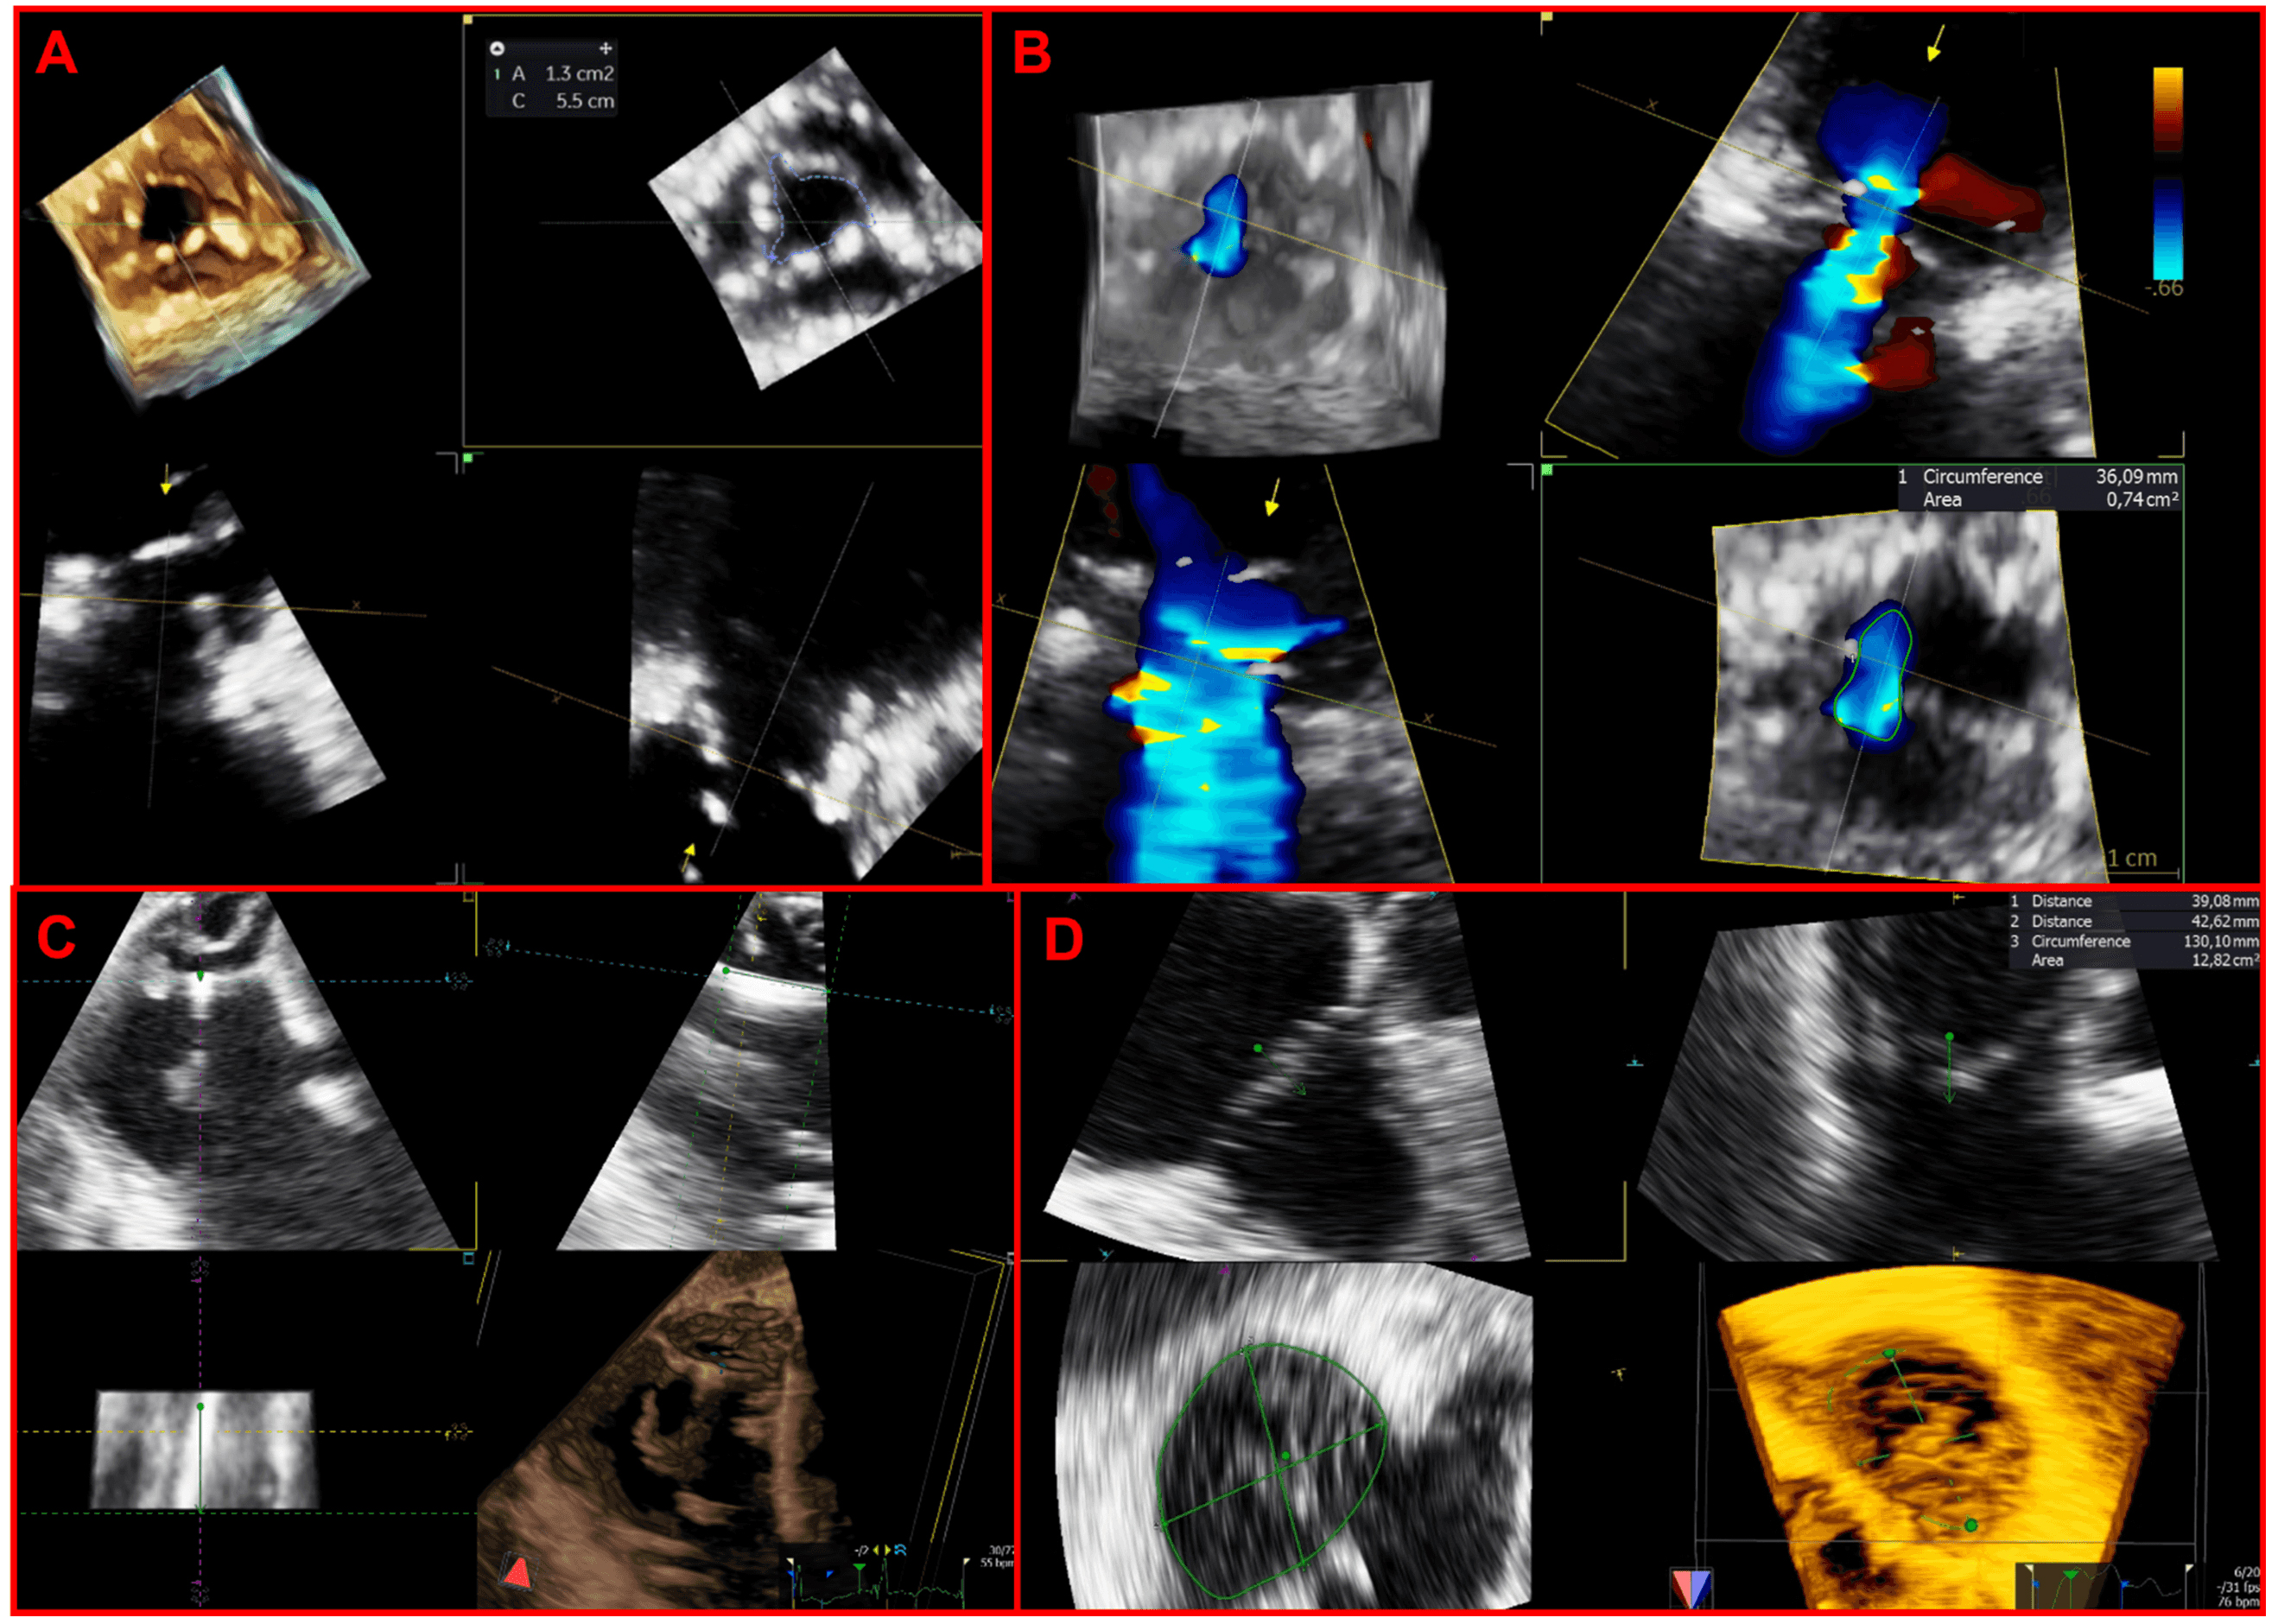

Unlimited useful information may be derived from high-quality 3D datasets thanks to offline MPR, which permit an in-depth exploration of the multiple 2D planes included within the acquired 3D volume at any point in the cardiac cycle (Fig. 2).

Fig. 2.Applications of multiplanar reconstructions of 3D datasets of the tricuspid valve. (A) 3D multiplanar reconstruction of a stenotic tricuspid bioprosthetic valve, used to planimeter the residual bioprosthetic orifice area. (B) Multiplanar reconstruction of a 3D color-Doppler volume dataset for quantification of regurgitant vena contracta area. (C) 3D multiplanar reconstruction used to assess the transvalvular trajectory of a CIED-lead during the entire cardiac cycle and its relationships with leaflets and the subvalvular apparatus. (D) 3D multiplanar reconstruction used to planimeter the annular perimeter, area and diameters.